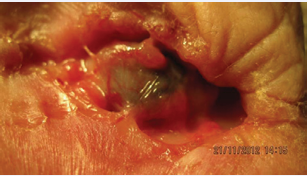

Infiltration of the orbit was in 1 case - see Figure 3;

Figure 3 Patient with basal cell of the lower eyelid without treatment in stage 4 coming to our Dept. with infiltration of the orbit (author A. Furdova, Dept of Ophthalmology, Medical School Comenius Univ., Bratislava).

in this patient due to infiltration of the orbit exenteration of the orbit was necessary.